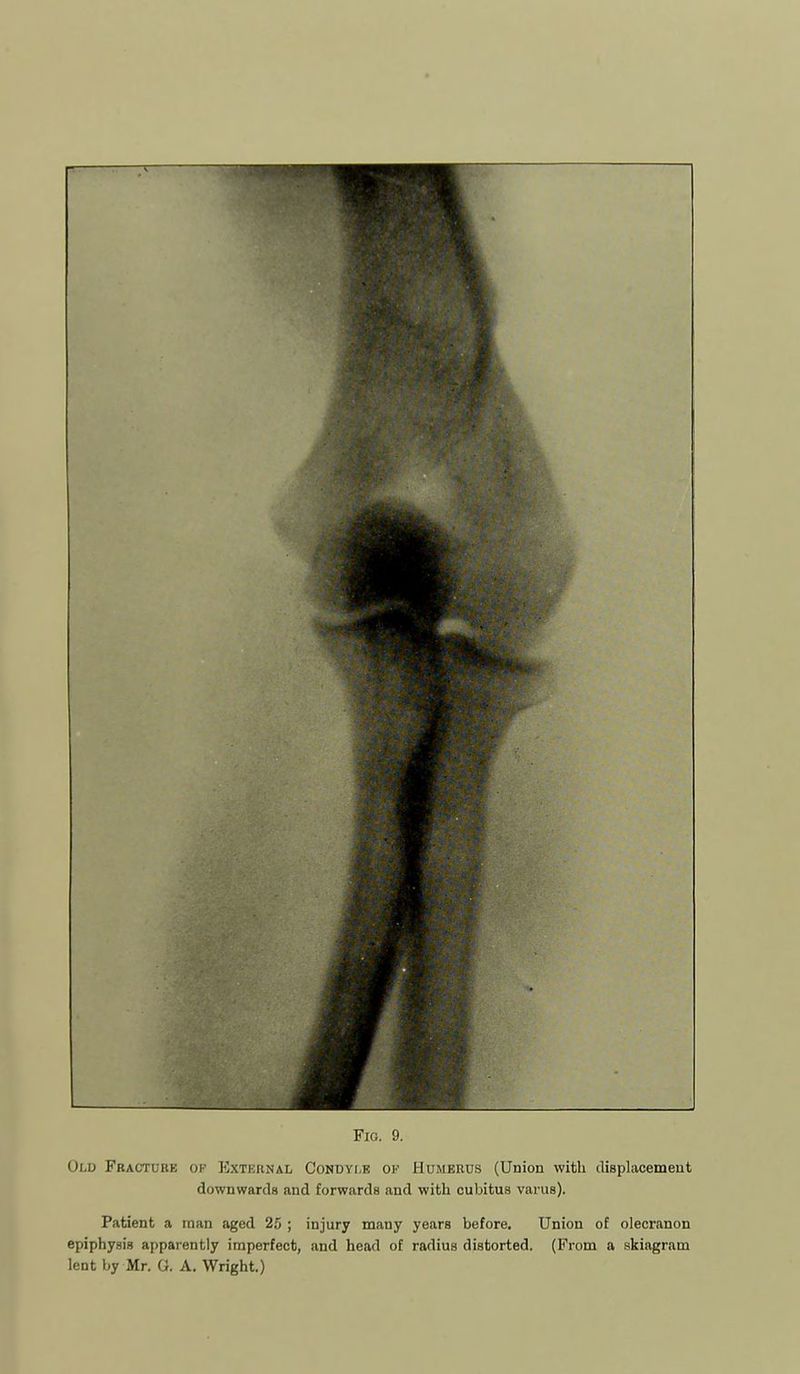

83/278 page 65